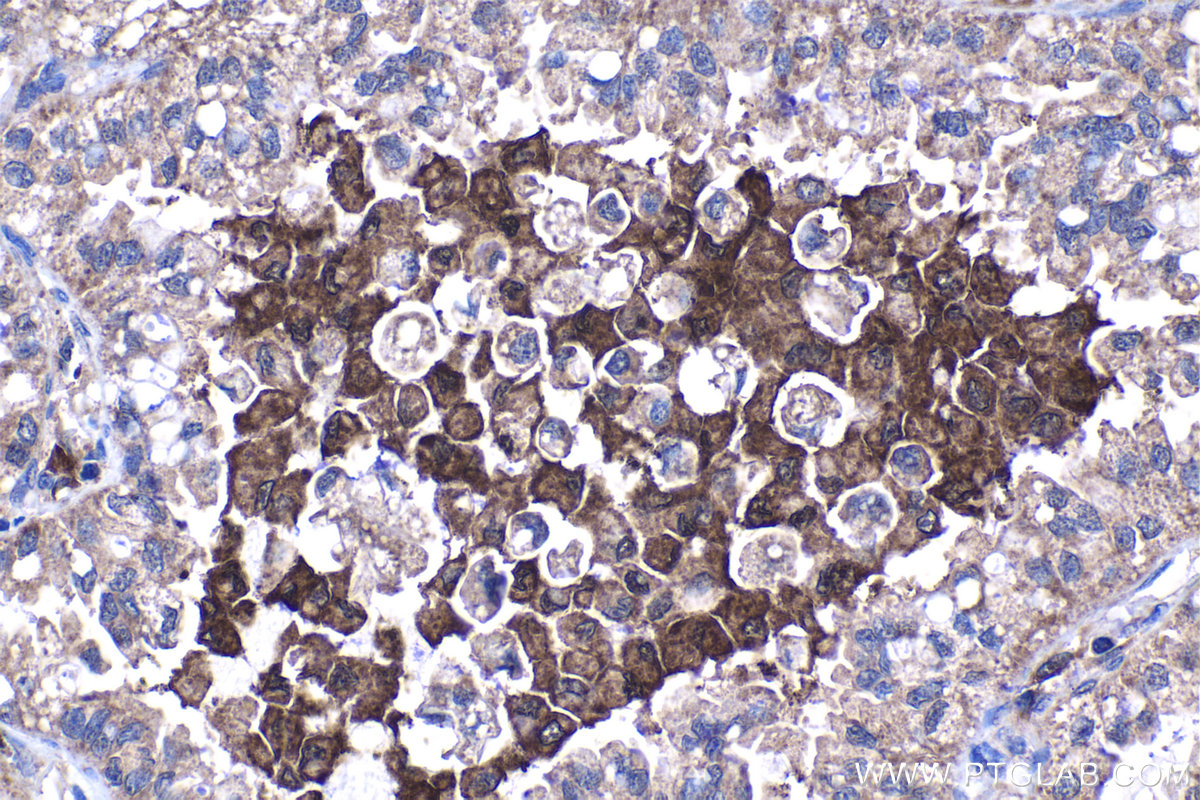

| Positive IHC detected in | human liver tissue, human lung cancer tissue Note: suggested antigen retrieval with TE buffer pH 9.0; (*) Alternatively, antigen retrieval may be performed with citrate buffer pH 6.0 |

| Immunohistochemistry (IHC) | IHC : 1:20-1:200 |